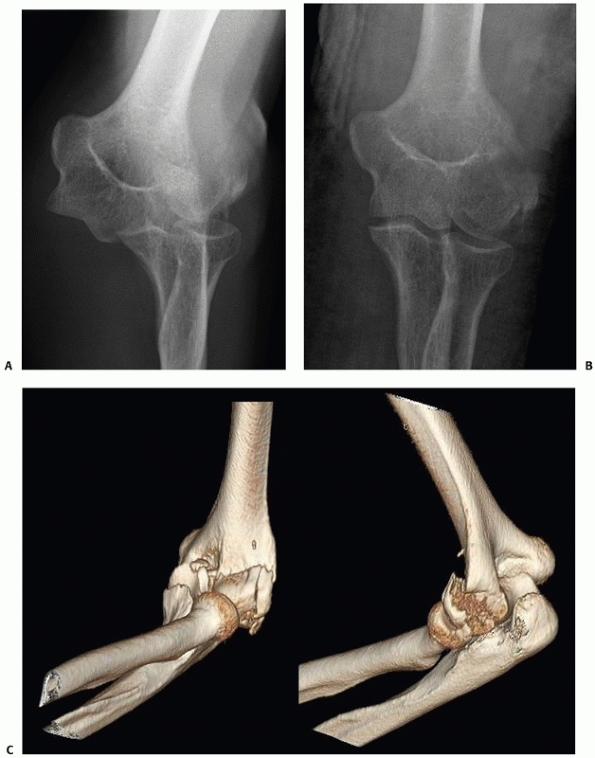

FIGURE 33-18

A 73-year-old woman with a comminuted intra-articular fracture of the medial column (AO/OTA type B1.3) treated with ORIF via an olecranon osteotomy (A-C). |